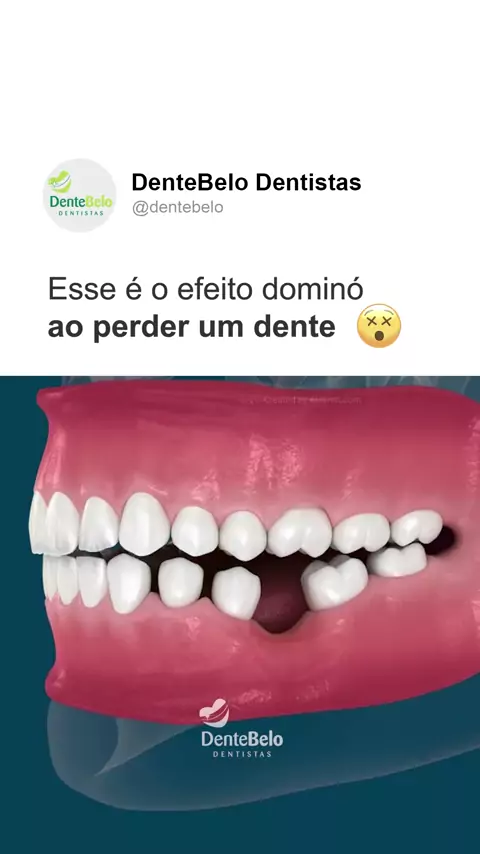

🦷 Perder um dente pode parecer um detalhe, mas é como um efeito dominó: aos poucos, outros dentes se movimentam, a mordida muda e a saúde bucal fica em risco. Cuide do seu sorriso hoje para evitar problemas maiores amanhã. 💚